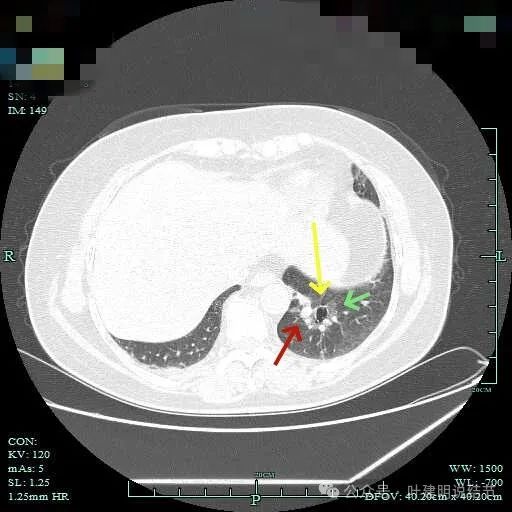

磨玻璃成分更明显,实性成分也明显,实性部分收缩力不强,表面不平整,感觉边缘毛糙。

表面浅分叶,磨玻璃成分明显,实性部分密度较高。

表面不平,磨玻璃部分的轮廓与边界清,实性部分占比不小,缺乏收缩力,像是腺泡型。